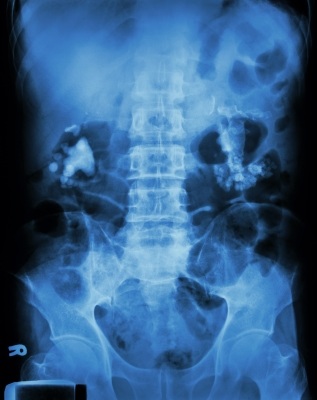

CT scan abdominopelvis merupakan pencitraan pilihan untuk mengidentifikasi batu ginjal. CT scan abdominopelvis dapat mengetahui lokasi, diameter, dan densitas batu. Apabila tidak tersedia, USG merupakan alternatif yang baik. USG juga dapat mengidentifikasi hidronefrosis atau dilatasi uretra.